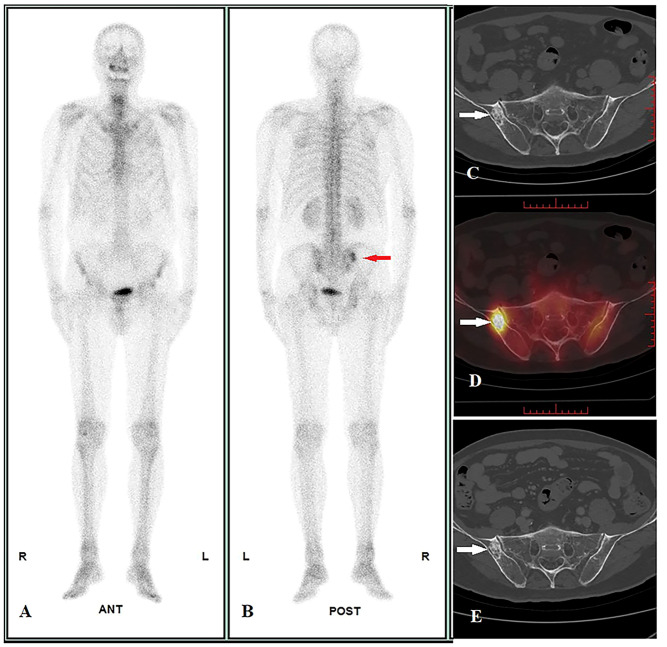

Donna di 47 anni con carcinoma neuroendocrino polmonare in stadiazione pre-trattamento.

L’imaging funzionale ha rilevato una chiara ipercaptazione patologica alla vertebra L5, caratterizzata da un elevato valore quantitativo (SUVmax = 45.41). Tuttavia, l’imaging morfologico (TC) iniziale era completamente negativo, non mostrando alterazioni strutturali dell’osso (C).

A distanza di tempo, l’esame TC di controllo ha documentato l’insorgenza di reazione osteoblastica (sclerosi) esattamente nello stesso punto segnalato dalla SPECT/TC mesi prima (E).

Questo caso “vero positivo” dimostra l’eccellente sensibilità dell’imaging scintigrafico (e in particolare della SPECT/TC quantitativa) nell’identificare micrometastasi o lesioni ossee in fase estremamente precoce, con largo anticipo rispetto alla comparsa dei segni morfologici visibili alla radiologia tradizionale.